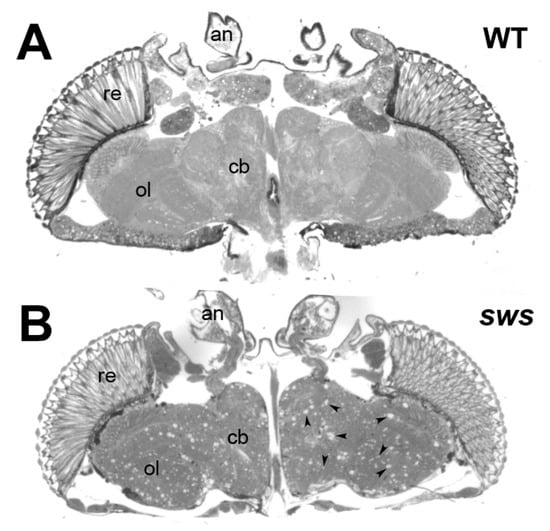

- Dutta, S.; Rieche, F.; Eckl, N.; Duch, C.; Kretzschmar, D. Glial expression of Swiss cheese (SWS), the Drosophila orthologue of neuropathy target esterase (NTE), is required for neuronal ensheathment and function. Dis. Models Mech. 2016, 9, 283–294. [Google Scholar] [CrossRef]